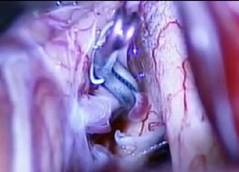

前交通動脈瘤顯微夾閉術: